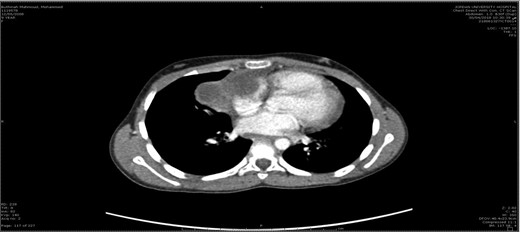

The mass was attached to pericardium, compressing the right atrium and encased the right phrenic nerve (Fig. 3). The mass en-bloc excision and thymectomy revealed multiloculate well-defined cyst measuring 6 cm in maximum dimension. Upon opening the cyst, and the pericardium yellowish sebaceous and cheesy material was found and identified as ruptured mature cystic teratoma with inflammatory reaction. Microscopy showed a ruptured mature cystic teratoma with inflammatory reaction (showing an unremarkable squamous, respiratory and gastric types epithelium, mature adipose tissue, smooth muscle tissue, and skin adnexa), with an unremarkable thymic tissue and no immature elements or malignancy.